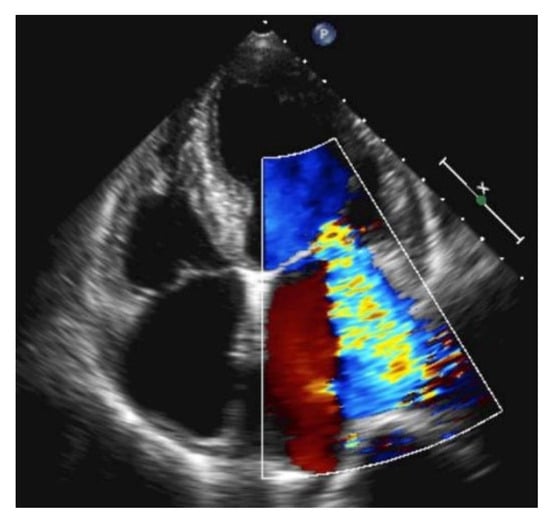

Recently, a number of POCUS devices have been including rapidly performed artificial intelligence (AI)-based EF assessment applications from one or more of the three windows. These AI EF applications can be highly accurate in real time when compared to comprehensive echocardiographic EF assessment and are likely to keep improving. Heart failure can also be caused by severe mitral regurgitation (e.g., papillary muscle rupture). In this case, the LVEF is normal or hyperdynamic. Severe mitral regurgitation can be seen with color Doppler over the mitral valve. In severe cases, the regurgitation jet reaches the apex of the left atrium (Figure 14).

Figure 14.

Large mitral regurgitation in apical four chamber view reaches the apex of the left atrium.